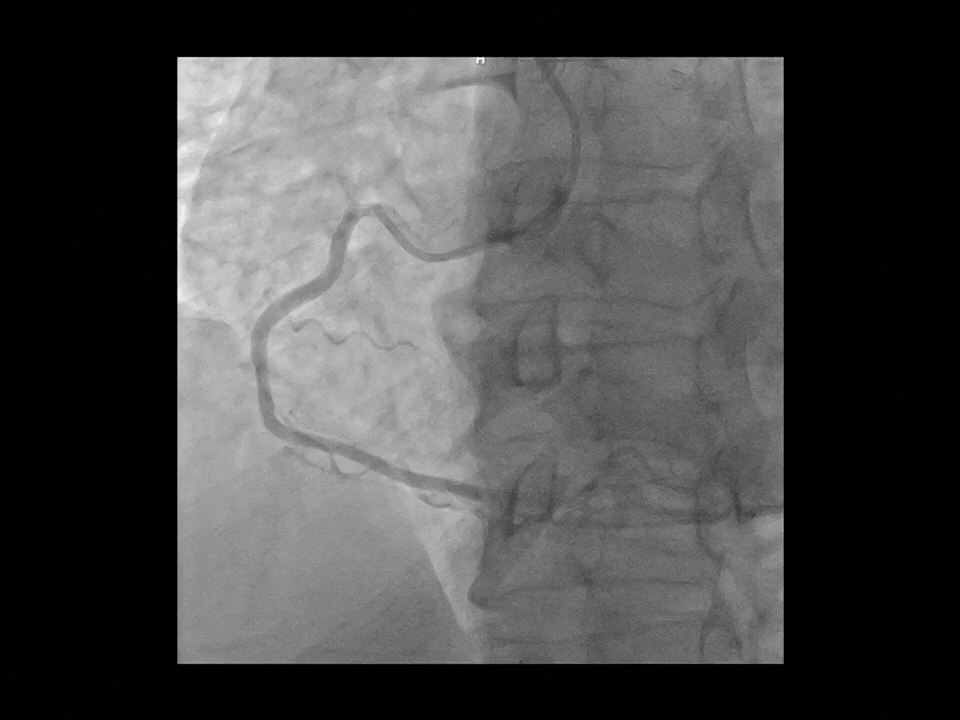

Hartă coronariană dinamică*

Dynamic Coronary Roadmap (DCR), o tehnologie avansată dezvoltată de UIH, oferă vizualizare în timp real a arterelor coronare, compensând automat mișcarea acestora. Prin suprapunerea angiogramei evidențiate peste imaginile fluoroscopice 2D live, DCR generează o hartă color adaptivă care se ajustează continuu în funcție de mișcarea coronariană. Această ghidare dinamică îmbunătățește precizia și eficiența în navigarea firelor și cateterelor, simplificând procedurile complexe.

uStent Live*

Vizualizarea îmbunătățită în timp real permite poziționarea și implantarea precisă a baloanelor, stenturilor și scaffoldu-rilor vasculare bioresorbabile, contribuind la optimizarea fluxului de lucru și reducerea timpului procedural.